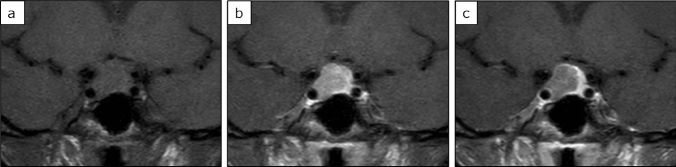

所見:成長ホルモン(GH)産生下垂体腺腫のある44歳の女性(a) 非造影T1強調画像では、腫瘍は脳と等信号です。(b) 早期相では弱く造影され、(c) 遅延相では造影剤のwashoutが認められます。腫瘍の洗い出し率(WR)は比較的高く(44.5%)、早期強化比(EER)は比較的低く(86.6%)、遅延強化比(DER)は比較的低い(48%)で、これはGH産生腺腫に共通するパターンです。